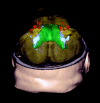

Background and purpose: Detection of longitudinal changes in white matter hyperintensities (WMH) by using visual rating scales is problematic. We compared a widely used visual rating scale with a volumetric method to study longitudinal white matter changes.

Methods: WMH were assessed with the visual Scheltens scale and a volumetric method in 100 elderly subjects aged 70-81 years for whom repetitive MR images were available with an interval of 33 (SD, 1.4) months. Reliability was determined by intraclass correlation coefficients. To examine the sensitivity of both the visual and volumetric method, we calculated Spearman rank correlations of WMH ratings and volume measurements with age.

Results: Reliability of the visual rating scale was good, whereas reliability of the volumetric measurement was excellent. For baseline measurements of WMH, we found weaker associations between WMH and age when assessed with the visual scale (r = 0.20, P = .045) than with the volumetric method (r = 0.31, P = .002). Longitudinal evaluation of WMH assessments showed regression in 26% of the subjects when analyzed with the visual rating scale against 12% of the subjects when using volumetric measurements. Compared with the visual rating, the correlation between progression in WMH and age was twice as high when using the volumetric measurement (r = 0.19, P = .062 and r = 0.39, P < .001, respectively).

Conclusion: Volumetric measurements of WMH offer a more reliable, sensitive, and objective alternative to visual rating scales in studying longitudinal white matter changes.